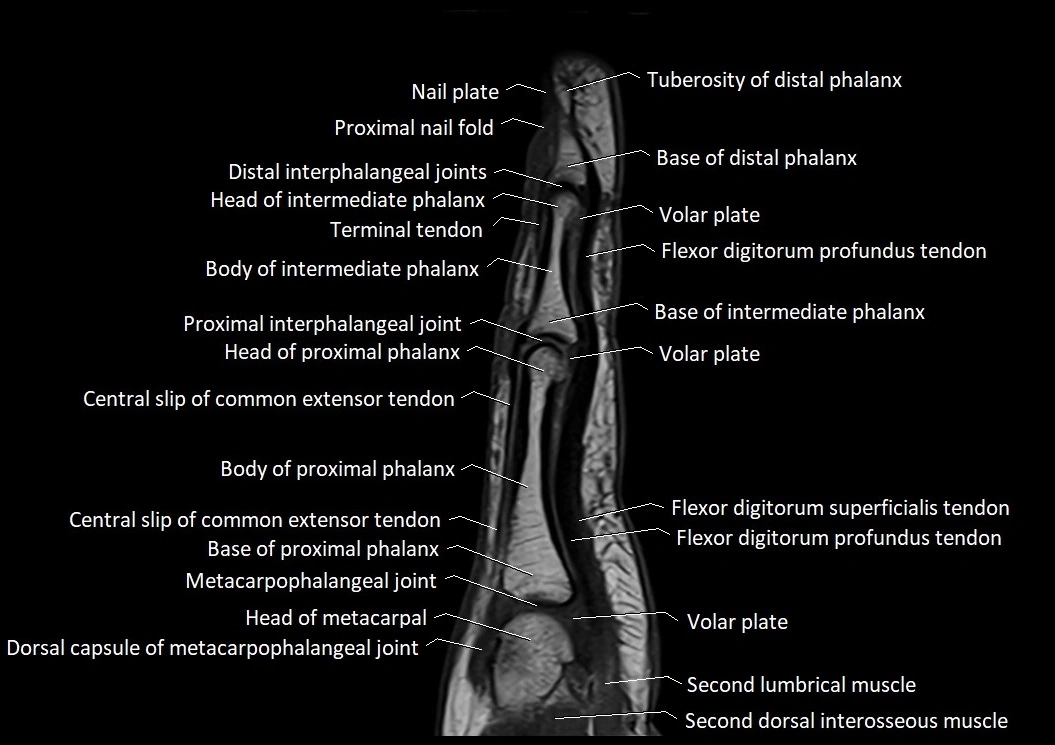

MRI images

image